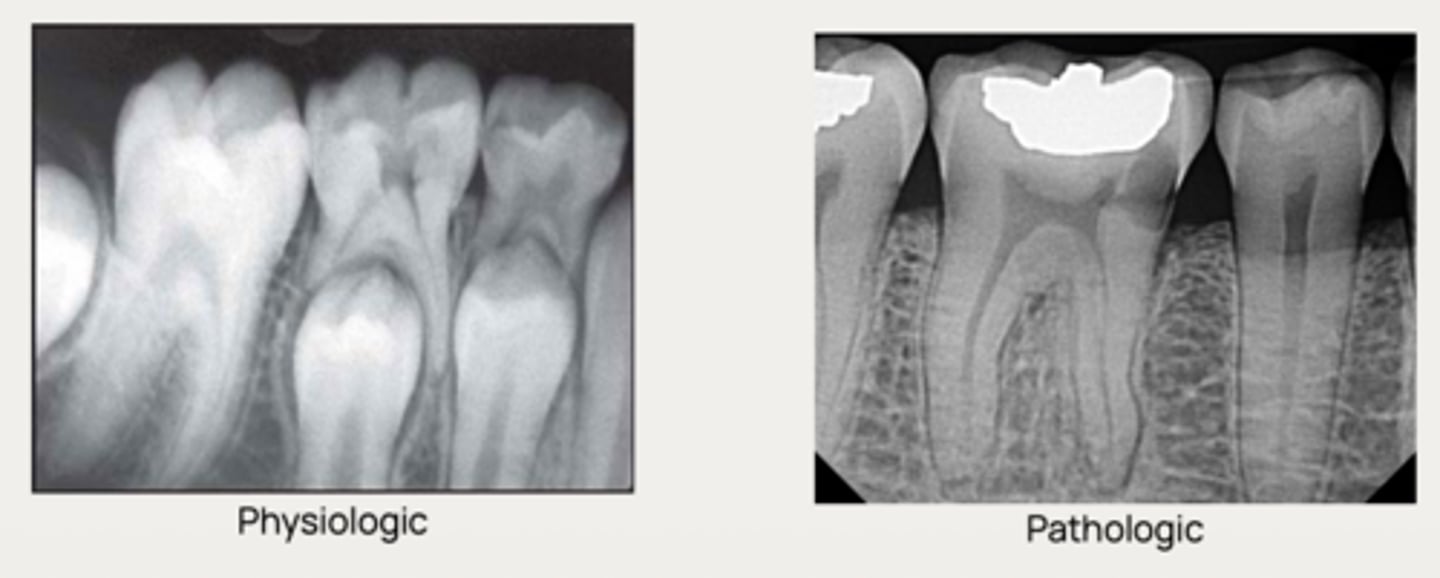

Internal root resorption

What type of resorption is the following?

- Originates inside the tooth, on the root canal wall

- Initiated by damage to the odontoblastic and

unmineralized predentin layer, resulting in →

- - Exposure of mineralized dentin to pulp tissue

- - Migration of odontoclasts to the site of injury

- - Resorption of the altered root canal walls

Internal inflammatory resorption

What is the diagnosis?

- Symmetrical ballooning of root canal

- Lesion does not move when PA is taken from different angles

- Usually does not have periapical lesion (Apical portion of root is vital!)

- Lesion may perforate into alveolar bone

- CBCT is recommended